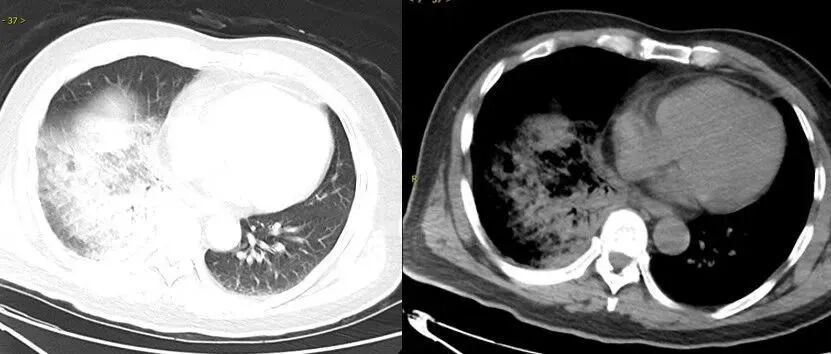

△鹦鹉热衣原体肺炎影像示例

图源:健康广东

相比于一般细菌引起的肺炎,鹦鹉热常伴有各种各样的肺外表现,如神经系统症状(头痛、精神状态改变)、消化道症状(呕吐、腹痛,肝功能异常)。

部分病例可致重症肺炎,甚至出现呼吸衰竭、心肌炎、脑炎等严重并发症,危及生命。